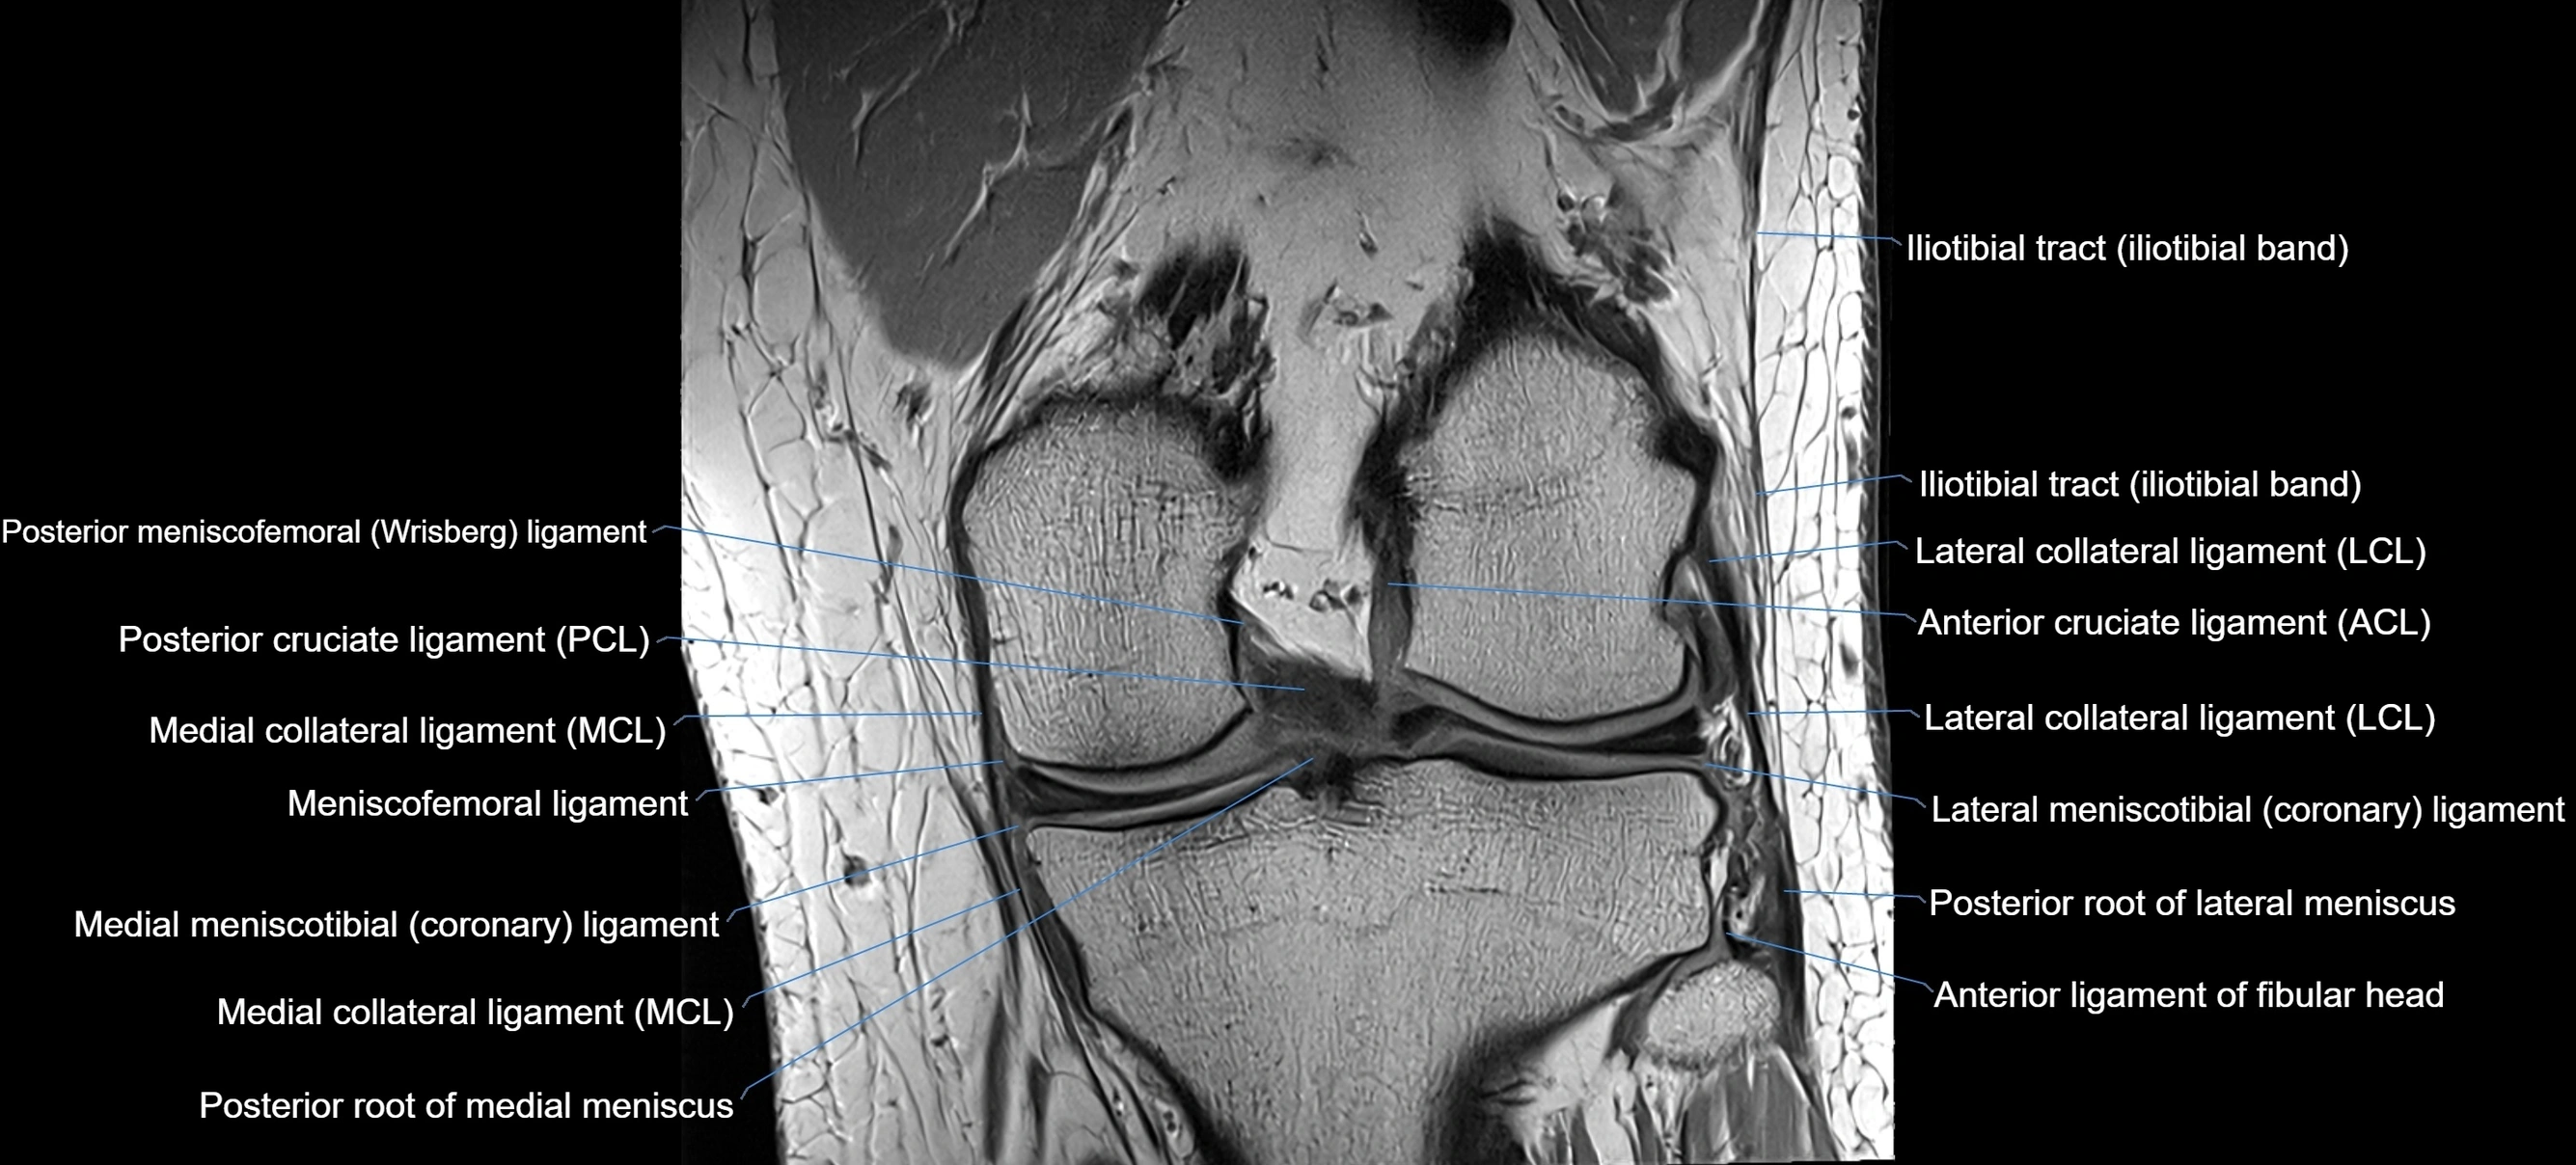

MRI images

image